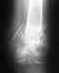

Неправильно сросшийся перелом пяточной и таранной кости

Здравствуйте, уважаемые доктора! Нужен совет - как можно исправить неправильно сросшийся перелом пяточной кости.

После снятия гипса, как смогла наступать на ногу с минимальной нагрузкой, выяснилось, что пятка неправильно срослась, деформирована стопа, заваливалась наружу, нога вставала на ребро, длина стопы уменьшилась на 2 см.

Носила обувь с ортопедическими стельками. Стопа частично выправилась, но деформация все равно осталась достаточно большая, из-за этого я не могу долго ходить, нога быстро устаёт, остаётся хромота, в районе голеностопного сустава остаётся небольшой отек, начались боли в тазобедренном суставе и спине.